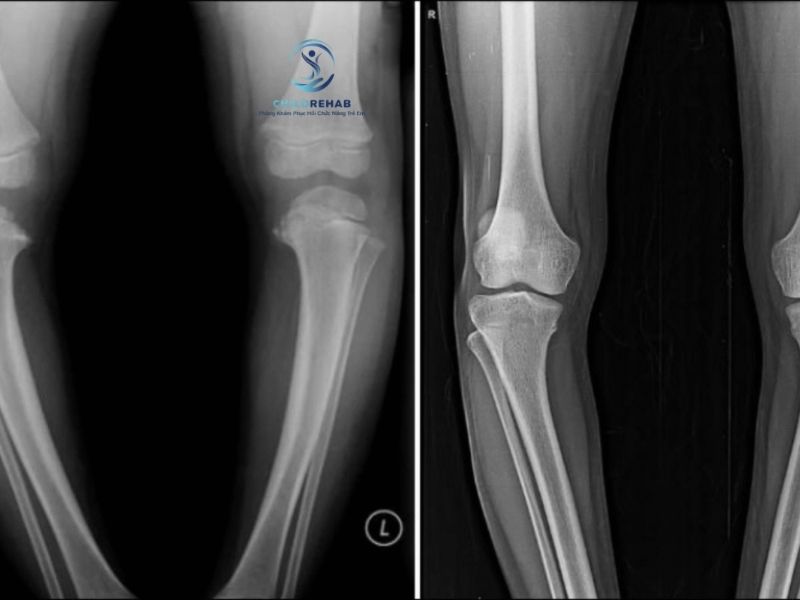

Không phải trường hợp nào chân chữ O ở trẻ cũng cần chụp X-quang. Tìm hiểu khi nào cần thêm đánh giá hình ảnh.